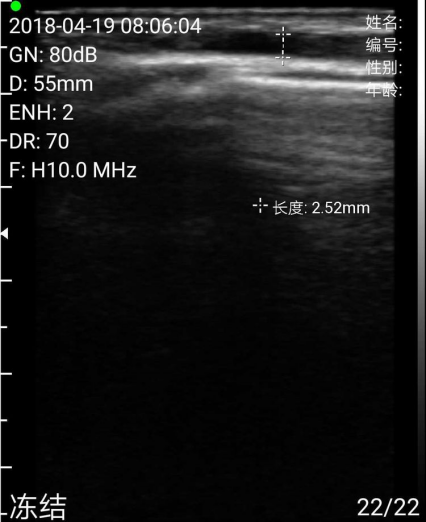

测量贵要静脉直径如图。均在满意范围,遂决定行右上肢尺动脉贵要静脉内瘘成形术。